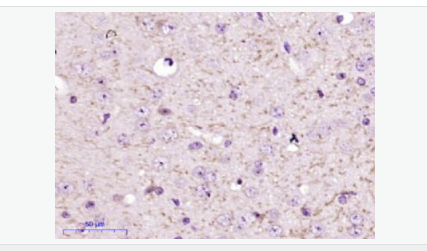

產(chǎn)品應(yīng)用WB=1:500-2000 ELISA=1:5000-10000 IHC-P=1:100-500 IHC-F=1:100-500 ICC=1:100-500 IF=1:100-500 (石蠟切片需做抗原修復(fù))

產(chǎn)品介紹FBXO2 is a 296 amino acid protein that contains one F-box domain and one F-box associated domain. Functioning as a component of the SCF complex, FBXO2 is thought to recognize and bind to select phosphorylated proteins, thereby promoting their ubiquitination and subsequent degradation.

Substrate recognition component of a SCF (SKP1-CUL1-F-box protein) E3 ubiquitin-protein ligase complex that mediates the ubiquitination and subsequent proteasomal degradation of target proteins. Involved in the endoplasmic reticulum-associated degradation pathway (ERAD) for misfolded lumenal proteins by recognizing and binding sugar chains on unfolded glycoproteins that are retrotranslocated into the cytosol and promoting their ubiquitination and subsequent degradation. Prevents formation of cytosolic aggregates of unfolded glycoproteins that have been retrotranslocated into the cytosol. Able to recognize and bind denatured glycoproteins, preferentially those of the high-mannose type.

Subcellular Location:

Cytoplasm. Microsome membrane.